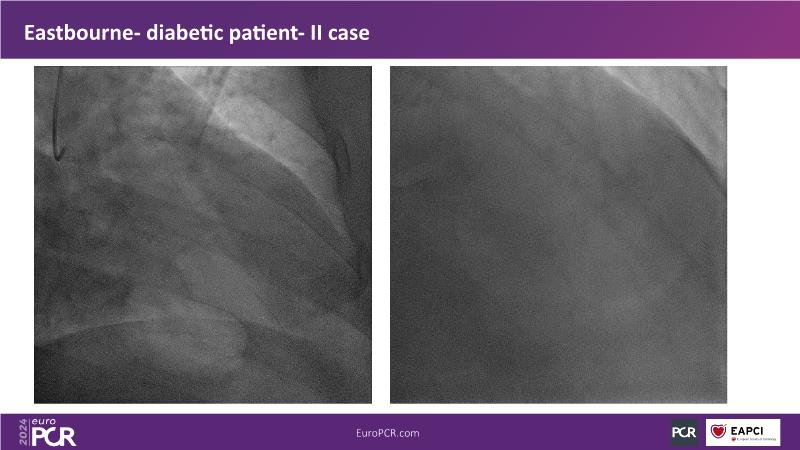

Browse this EuroPCR 2024 session to explore the safety and efficacy of sirolimus-coated balloons from pre-clinical data, review MagicTouch data from real-world populations with case-based examples, and learn about the MagicTouch sirolimus-coated balloon clinical programs. Discover insights and takeaways from the significance of the EASTBOURNE subgroups, and analyze the challenges and opportunities in PCI for diabetic patients.